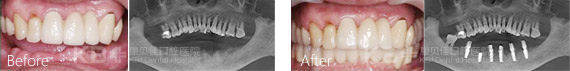

南京康贝佳口腔种植科主任冯观保介绍,王阿姨这种技术叫做即刻种植牙。相比于传统种植牙即刻种植无需等待,当天就能戴上牙冠。即刻种植技术具有稳固牢靠、舒适美观、安全快速、不伤健康邻牙等独特优势,是当前采用率高的种植方式。

即刻种植牙适应症广,特别是半口或者全口牙缺失,康贝佳口腔给您推荐ALL-ON 4种植技术。ALL-ON 4只需四颗种植体即可恢复半口牙,大大节省了费用。并且ALL-ON 4种植牙无骨量限制,再糟糕的口腔环境也能成功种上一口好牙。